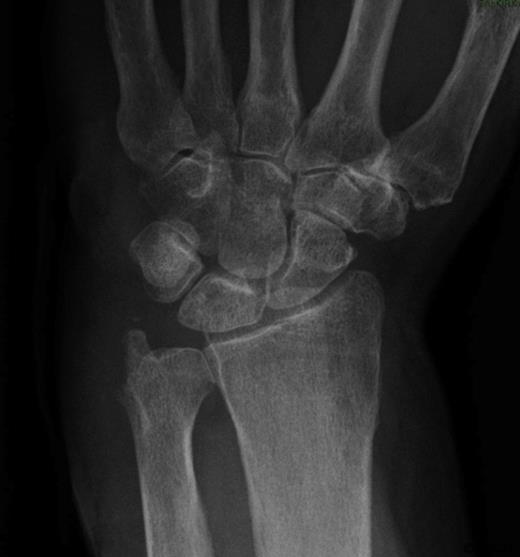

The patient agreed to a repeat biopsy and excision of the necrotic bone (Figure 4). Microscopy of the specimen again showed a florid granulomatous inflammatory process with areas of fibrinoid necrosis. Cultures isolated Mycobacterium tuberculosis.

Post-operative Xray of the wrist showing excision of the ulnar styloid